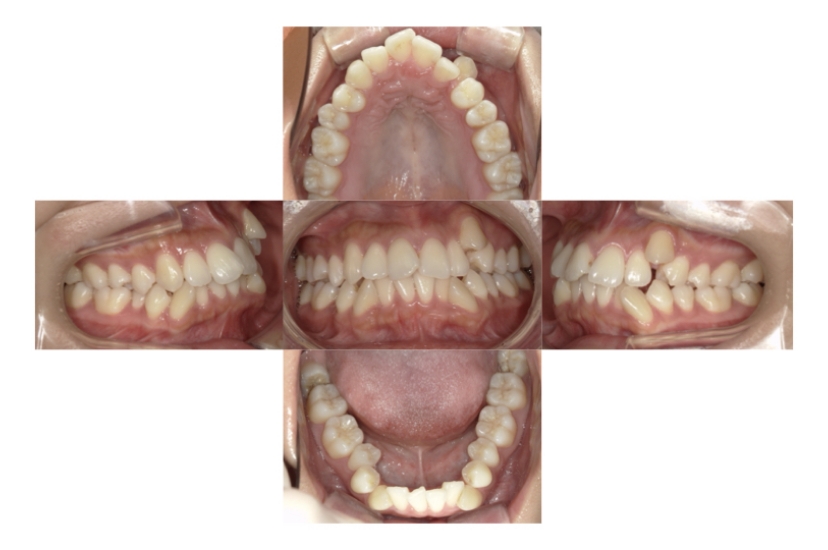

BEFORE

AFTER

上顎前突、叢生

抜歯

ブラケット矯正

上下顎叢生、上顎前突(出っ歯、上下の前歯のガタガタ)のケースです。

装置はラビアル(上下表側)で、上顎の小臼歯を2本抜歯を行っています。抜歯したスペースを使って、上の前歯の後方移動と叢生(ガタガタ)と出っ歯の改善を行っています。下は歯と歯の間にIPR(隣接面削合)を行い、スペースを確保し、叢生の改善を行っています。

主訴 前歯のガタガタと出っ歯が気になる。

年齢・性別 47歳 女性

お住まいの地域 神奈川県川崎市

治療方針 抜歯スペースおよびIPRを利用して上前歯の叢生(ガタガタ)の改善

抜歯部位 上顎左右第一小臼歯

使用装置 ラビアル(上下表側)、顎間ゴム

治療期間 2年0か月

治療回数 15回

リテーナー クリアリテーナー